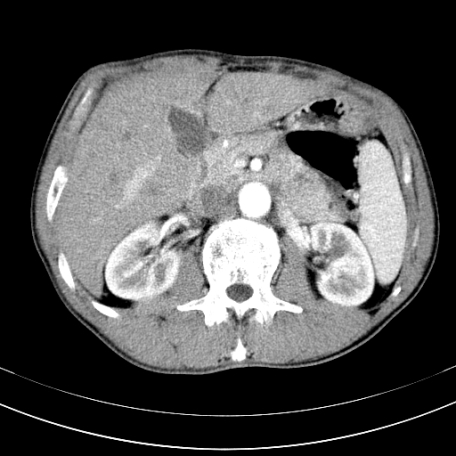

标题: CT21441:男55岁,上腹部胀痛半年余,请老师们看看是后腹膜淋巴 [打印本页]

标题: CT21441:男55岁,上腹部胀痛半年余,请老师们看看是后腹膜淋巴

腹主动脉右侧有一个,有肿瘤病史吗?

转移瘤或淋巴瘤

腹膜后淋巴结肿大,原因待查。

支持   腹膜后淋巴结肿大,原因待查